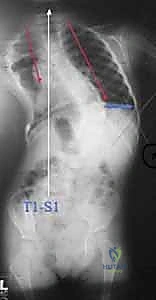

- الأشعة السينية (X-rays) البانورامية: يتم أخذ صور للعمود الفقري بالكامل من الأمام والخلف والجانب (أثناء وقوف الطفل أو جلوسه إذا كان لا يستطيع الوقوف). يتم من خلالها قياس "زاوية كوب" (Cobb Angle) لتحديد شدة الانحناء.

قضبان النمو (Growing Rods): الثورة في علاج جنف الأطفال المبكر

عندما يفشل العلاج التحفظي، وتتجاوز زاوية الجنف 50 درجة مع استمرار تدهور الحالة، يصبح التدخل الجراحي ضرورة حتمية لإنقاذ حياة الطفل وتأمين مستقبله. في الماضي، كانت جراحات دمج العمود الفقري للأطفال الصغار تؤدي إلى قصر القامة وتوقف نمو الرئتين.

الفكرة العبقرية وراء قضبان النمو هي "التثبيت دون الدمج". يقوم الدكتور هطيف بتثبيت العمود الفقري من الأعلى (عند الفقرات الصدرية العليا) ومن الأسفل (عند الفقرات القطنية أو الحوض) باستخدام مسامير أو خطاطيف تيتانيوم. يتم توصيل هذه المثبتات بقضبان معدنية قوية تمتد عبر منطقة الجنف.

الجزء الأهم: لا يتم دمج (تلحيم) العظام في المنطقة الوسطى المنحنية. هذا يسمح للعمود الفقري بالاستمرار في النمو. مع نمو الطفل، يتم "إطالة" هذه القضبان بشكل دوري لمواكبة زيادة طول الطفل وتصحيح الانحناء تدريجياً.